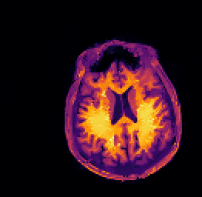

Refer to caption sinogram datafg

Refer to caption deformed ground truthfg Refer to caption deformed ground truthfg

Refer to caption side informationfg Refer to caption side informationfg

Refer to caption ground truthfg Refer to caption ground truthfg

Refer to caption FBPfg

SSIM 61.3%

RD n/a

Refer to caption TVTV\operatorname{TV}fg

SSIM 88.1%

Refer to caption three-stepfg

SSIM 93.3%

RD 6.5%

Refer to caption proposedfg

SSIM 93.6%

RD 3.1%

Figure 5: PET reconstructions with structural MR side information. Filtered back-projection (FBP) and TVTV\operatorname{TV} do not correct motion and yield poor reconstructions. Both the three-step and the proposed method correct the deformation and the reconstruction satisfyingly agrees with the ground truth. We give SSIM and RD values of the reconstructed images and deformation parameters. For FBP and TVTV\operatorname{TV} no deformation was corrected and SSIM is given with respect to the deformed ground truth.

In this experiment we consider PET-MR, where we aim to reconstruct a tracer distribution using a fully sampled T1-weighted MR image of size 144×144144144144\times 144 as side information. The forward operator is modelled by a parallel beam X-ray transform with 200 angles equispaced in (0,π]0𝜋(0,\pi] and 192 bins. The sinogram data were simulated using a ground truth image deformed with respect to the side information through the rigid deformation

ϕrigid(x)=Rθx+b,subscriptitalic-ϕrigid𝑥subscript𝑅𝜃𝑥𝑏\displaystyle\phi_{\texttt{rigid}}(x)=R_{\theta}x+b, (23)

where Rθsubscript𝑅𝜃R_{\theta} is a rotation matrix (12) with angle θ=0.15.7𝜃0.1superscript5.7\theta=0.1\approx 5.7^{\circ} and b=(0.02,0.08)T𝑏superscript0.020.08𝑇b=(0.02,0.08)^{T} is a translation vector.

In this experiment we simulate data based on a dTVdTV\operatorname{dTV}-regularized reconstruction of clinical data, see [28]. The data is an instance of a Poisson random variable with parameter Ax+r𝐴𝑥𝑟Ax+r, where the background r𝑟r is chosen as constant 7 and the forward operator is scaled to about 1.31061.3superscript1061.3\cdot 10^{6} expected counts in the data. Correspondingly, the data fidelity used is the Kullback–Leibler distance (4).

Again, images are in [1,1]2superscript112[-1,1]^{2} and hence the pixel width of the side information is 0.0138¯0.013¯80.013\overline{8}. The resolutions and regularization parameters in Algorithm 2 were chosen as nk=(92,182,362,722,1442)subscript𝑛𝑘superscript92superscript182superscript362superscript722superscript1442n_{k}=(9^{2},18^{2},36^{2},72^{2},144^{2}) and αk=4101(104,103,102,10,1)subscript𝛼𝑘4superscript101superscript104superscript103superscript102101\alpha_{k}=4\cdot 10^{-1}\cdot(10^{4},10^{3},10^{2},10,1). For the TVTV\operatorname{TV} experiment we used αk=4102(104,103,102,10,1)subscript𝛼𝑘4superscript102superscript104superscript103superscript102101\alpha_{k}=4\cdot 10^{-2}\cdot(10^{4},10^{3},10^{2},10,1).

The sinogram data and the deformed image which was used to generate the data are shown in the top row of Figure 5. Furthermore, we show the side information and the ground truth image. In the second row of Figure 5 we show four different reconstructions: the first one obtained through filtered back-projection, the second one utilizing TVTV\operatorname{TV} regularization, the third one using the three-step method (22), and the fourth one being the proposed method. The first two methods, which do not use the side information or correct any motion, exhibit poor image quality due to strong noise in the sinogram. On the other hand, both the three-step and the proposed method correct the deformation and the reconstructions are in very good agreement with the ground truth image.

Quantitatively, the SSIM values for filtered back-projection and TVTV\operatorname{TV} are relatively low whereas they are comparably high for both the three-step and the proposed method, with slightly better values for the proposed method. The same is also true for the relative errors of the computed deformation fields.